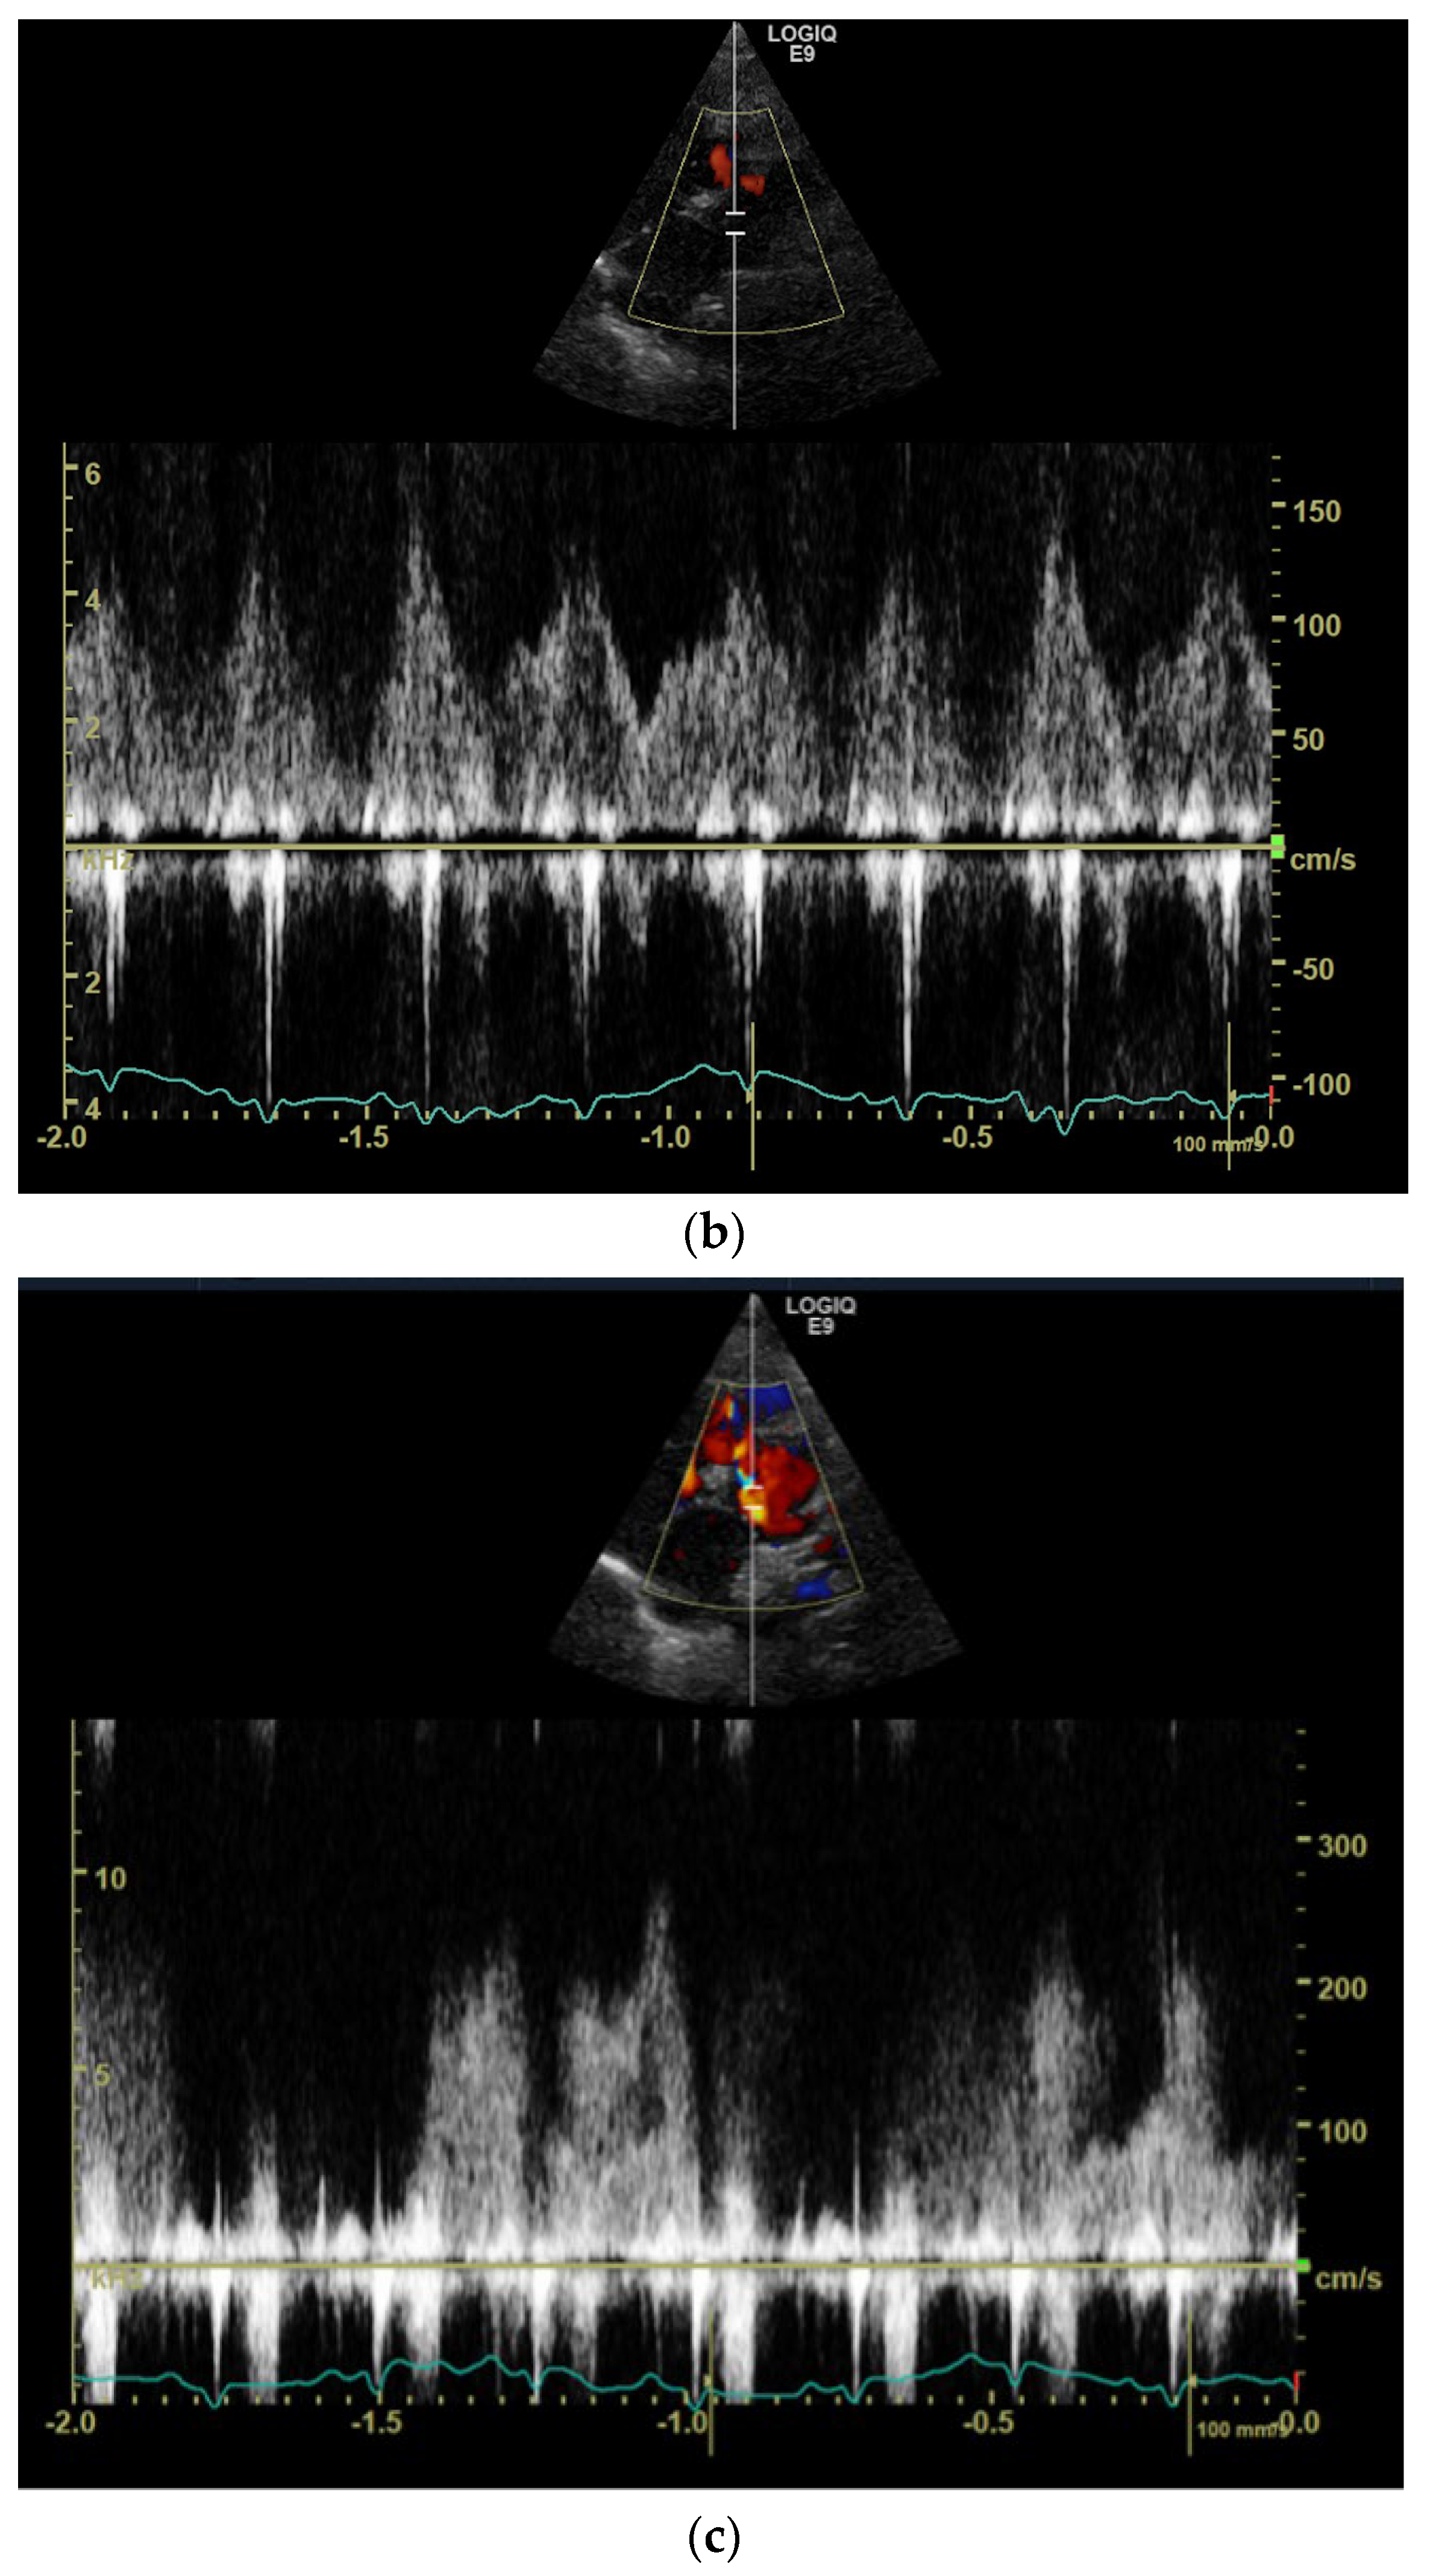

1. Case Description